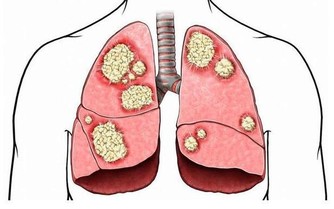

4、致使孩內分泌失調:

早熟會導致孩子內分泌失調,出現全身性多毛、減少、乾枯,甚至脫落等情況。